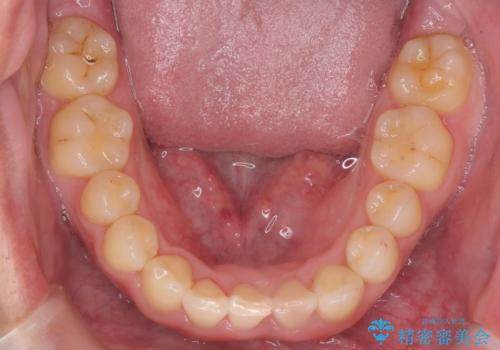

前歯のすき間 歯のがたつき

- 前歯のすき間とがたつきを主訴に来院。

右上の前歯は過去にがたつきがあったとのことで抜いてしまっていました。

歯の数を合わせるために、下の歯を1本抜いて矯正しています。

下の前歯を抜歯したことでブラックトライアングルができましたが、仕上げにIPRを加えることで目立たなくすることができました。